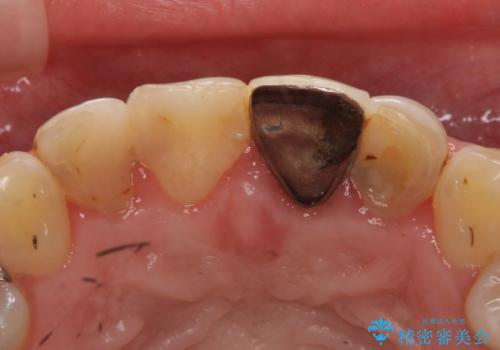

- 前歯の色・形を綺麗にしたいといらっしゃった方の症例です。

左上1、2の再根管治療終了後、オールセラミッククラウン(スペシャル)による補綴を行いました。